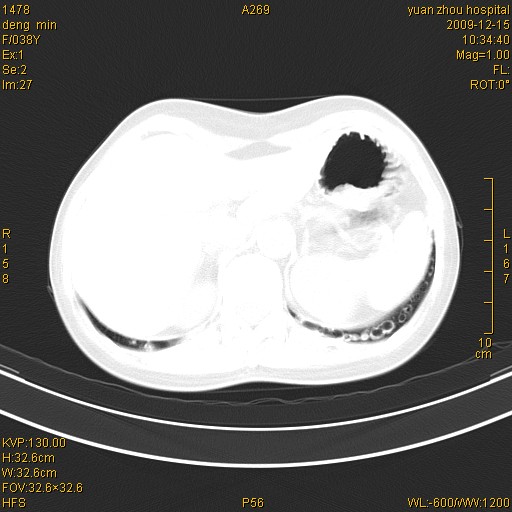

标题: CT23919:F38Y 咳嗽月余 [打印本页]

标题: CT23919:F38Y 咳嗽月余

右肺中下叶、左肺上叶舌段及左肺下叶支气管扩张合并感染。